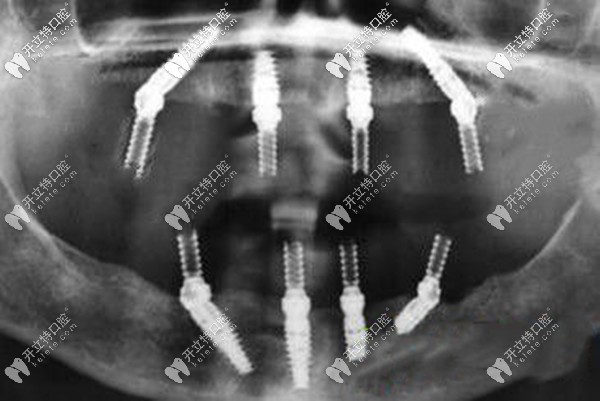

傳統(tǒng)的全口種植牙采用的是分段式種植,上下頜各植入8-10顆植體,對牙槽骨條件要求較高,而且植入種植體后還要等3-6個月后才能戴牙冠~~

如果,牙槽骨量不足,做ALL-ON-4全口即刻負重種植牙,不用植骨,上下頜各植入4顆種植體就能恢復(fù)全口的咀嚼功能,而且是當(dāng)天種牙當(dāng)天就能吃東西。

一般做all-on-4種植牙需要導(dǎo)板,而適合的種植體只有韓系和瑞典諾貝爾,年齡較大的可以選擇性價比高的韓系植體,半口的價格大概7萬起、全口13萬起;年輕或不差錢的就用瑞典諾貝爾種植體,半口16萬起、全口28萬起。